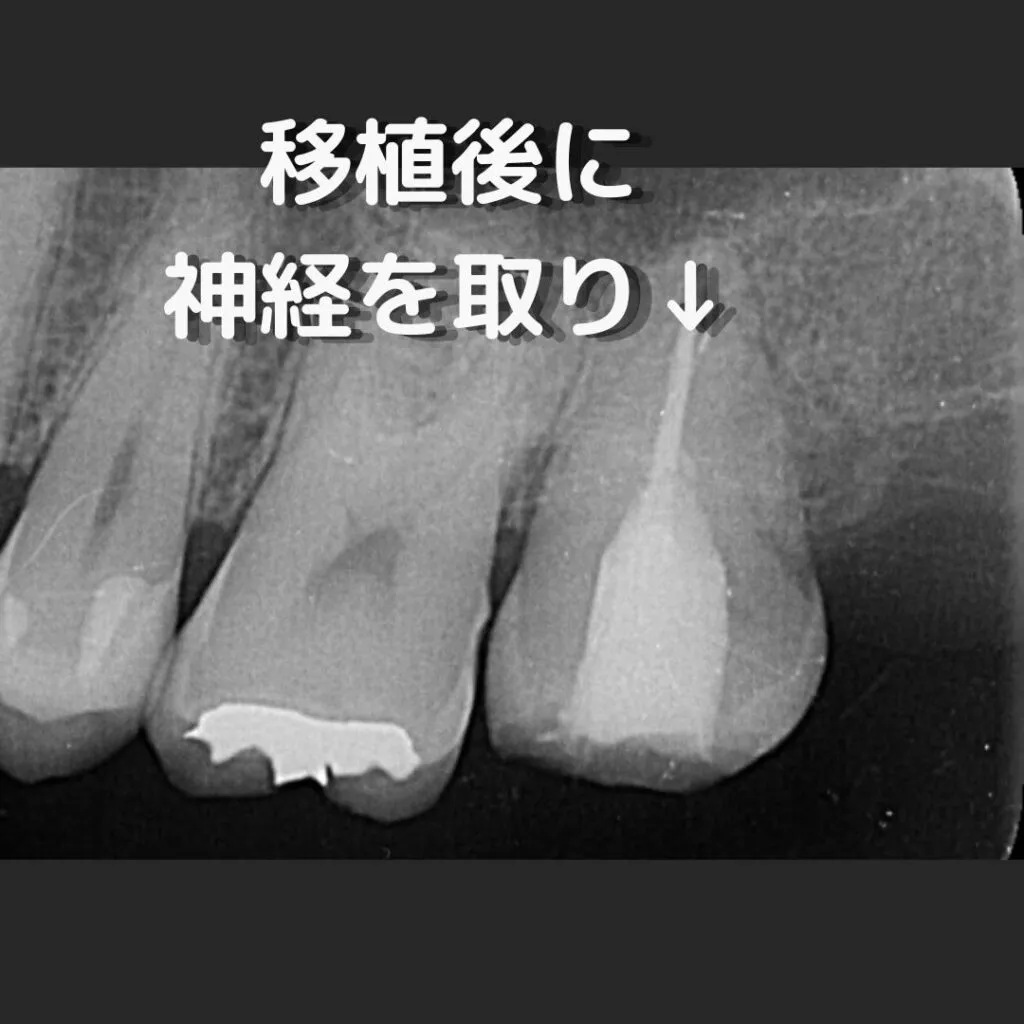

症例1(虫歯が大きく残せないため、親知らずを移植しました)

| 治療のリスクについて | タバコは傷の治りを悪くします。 出来るだけ禁煙していただくか、本数を減らしていただけるようお願いします。 静脈が多い所を切るので、内出血や腫れることがあります。 術後すぐは、歯が少し揺れます。 |

|---|---|

| 費用 | 移植手術…………………………………………………66,000円 顕微鏡を使用しての神経処置…………………………66,000円 被せ物(ジルコニア)………………………………126,500円 合計……………………………………………………258,500円 |

※すべて税込